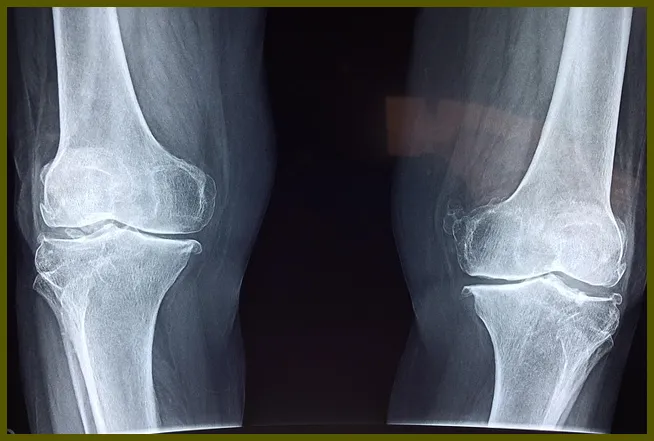

무릎연골 손상은 대개 외상이나 반복적인 스트레스로 인해 발생하는 증상입니다. 연골은 뼈와 뼈 사이에서 충격을 흡수하고 마찰을 줄이는 역할을 합니다. 그러나 이 연골이 손상되면 무릎 통증이나 불편함을 유발하게 됩니다. 이러한 증상은 일반적으로 노화, 사고, 혹은 비만 등 다양한 요인으로 인해 발생할 수 있습니다.

무릎연골 손상은 대개 두 가지 주요 유형으로 나눌 수 있습니다. 첫 번째는 단순한 마모로, 나이가 들면서 자연스럽게 발생하는 경우입니다. 두 번째는 사고나 부상으로 인한 급성 손상으로, 이 경우에는 통증과 함께 갑작스러운 움직임 제한이 동반될 수 있습니다.

무릎연골 손상이 발생할 때 나타나는 증상은 다양합니다. 일반적인 증상으로는 무릎 통증, 부기, 그리고 관절의 경직 등이 있습니다. 이러한 증상들은 개인의 상태에 따라 다르게 나타날 수 있습니다.

무릎의 통증은 연골 손상의 가장 흔한 증상입니다. 이 통증은 특정 동작을 할 때, 예를 들어 계단을 오르내릴 때 더욱 심해질 수 있습니다. 또한, 무릎을 구부릴 때 마찰음을 느끼거나, 무릎 부상 이후의 적절한 회복이 이루어지지 않았을 때 나타나는 불편함도 포함됩니다.